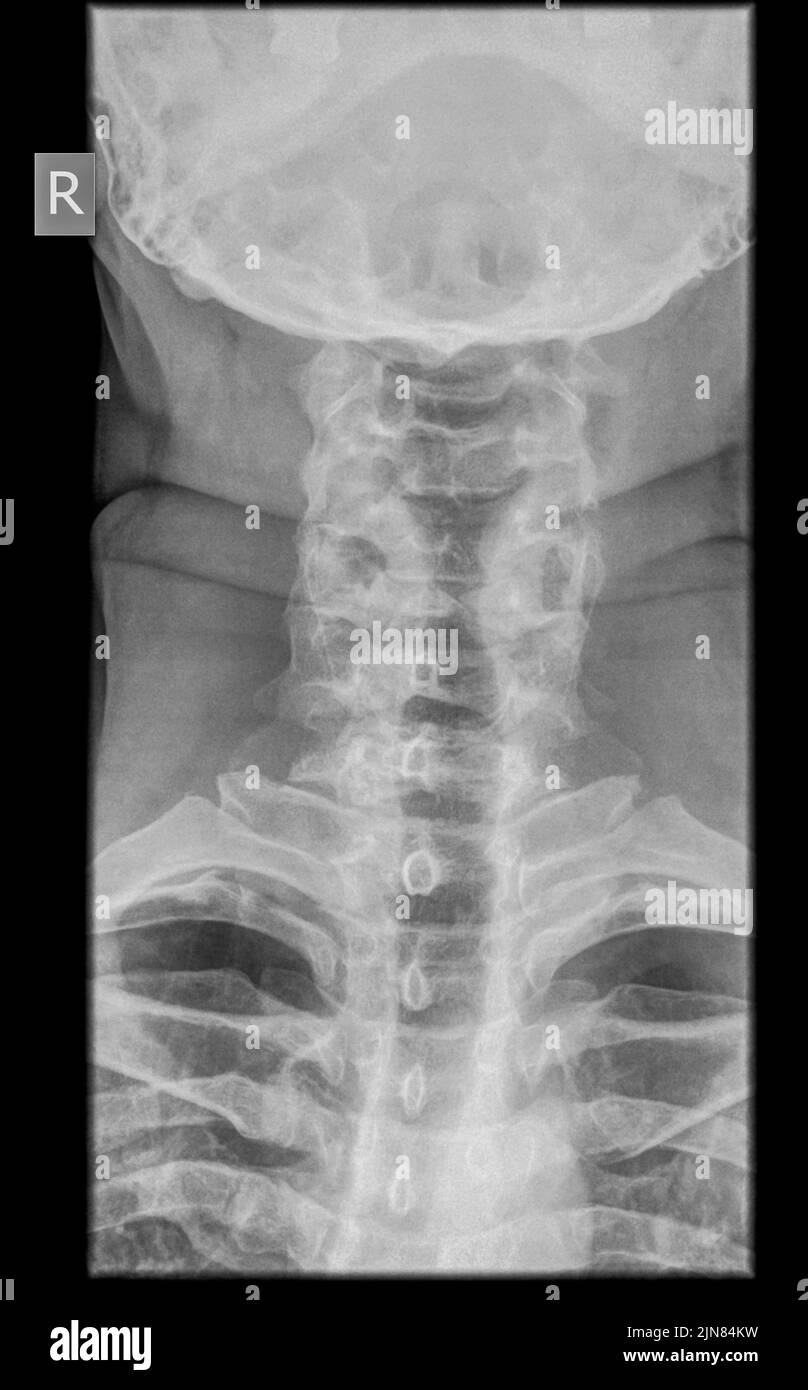

From www.sciencephoto.com

Dens fracture. Cervical spine xray Stock Image C019/7234 Science What Is Dens Fracture Type i, type ii, and type iii, depending on the location and morphology of the fracture.[1] the odontoid process, known. A fracture occurring in the body of the axis underlying the dens. This type of fracture is most common in older adults who fall and break off the odontoid in the cervical spine (neck). Odontoid fractures are relatively common fractures. What Is Dens Fracture.

From www.alamy.com

Dens fracture of the spine, Xray Stock Photo Alamy What Is Dens Fracture Type i, type ii, and type iii, depending on the location and morphology of the fracture.[1] the odontoid process, known. Odontoid process fracture, also known as a peg or dens fracture, occurs where there is a fracture through the odontoid process of c2. Treatment may take the form of surgery or wearing a. The odontoid is a bony. Lets take. What Is Dens Fracture.